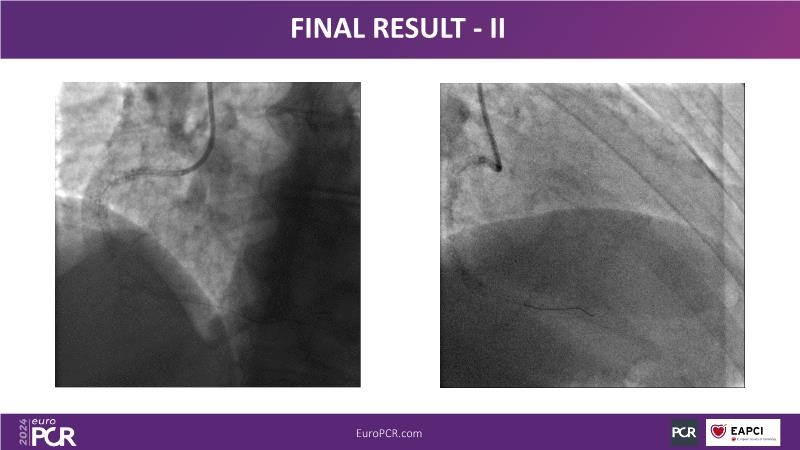

From innovation to reality: the impact of Cre8 EVO technology on complex PCI

This session is a good opportunity to delve into the contemporary technical and clinical complexities surrounding complex PCIs in challenging patient cases. Explore the necessary tools and treatment strategies to enhance peri-procedural and long-term clinical outcomes, and follow discussions on the unique technologies of Cre8 EVO in complex PCI scenarios.